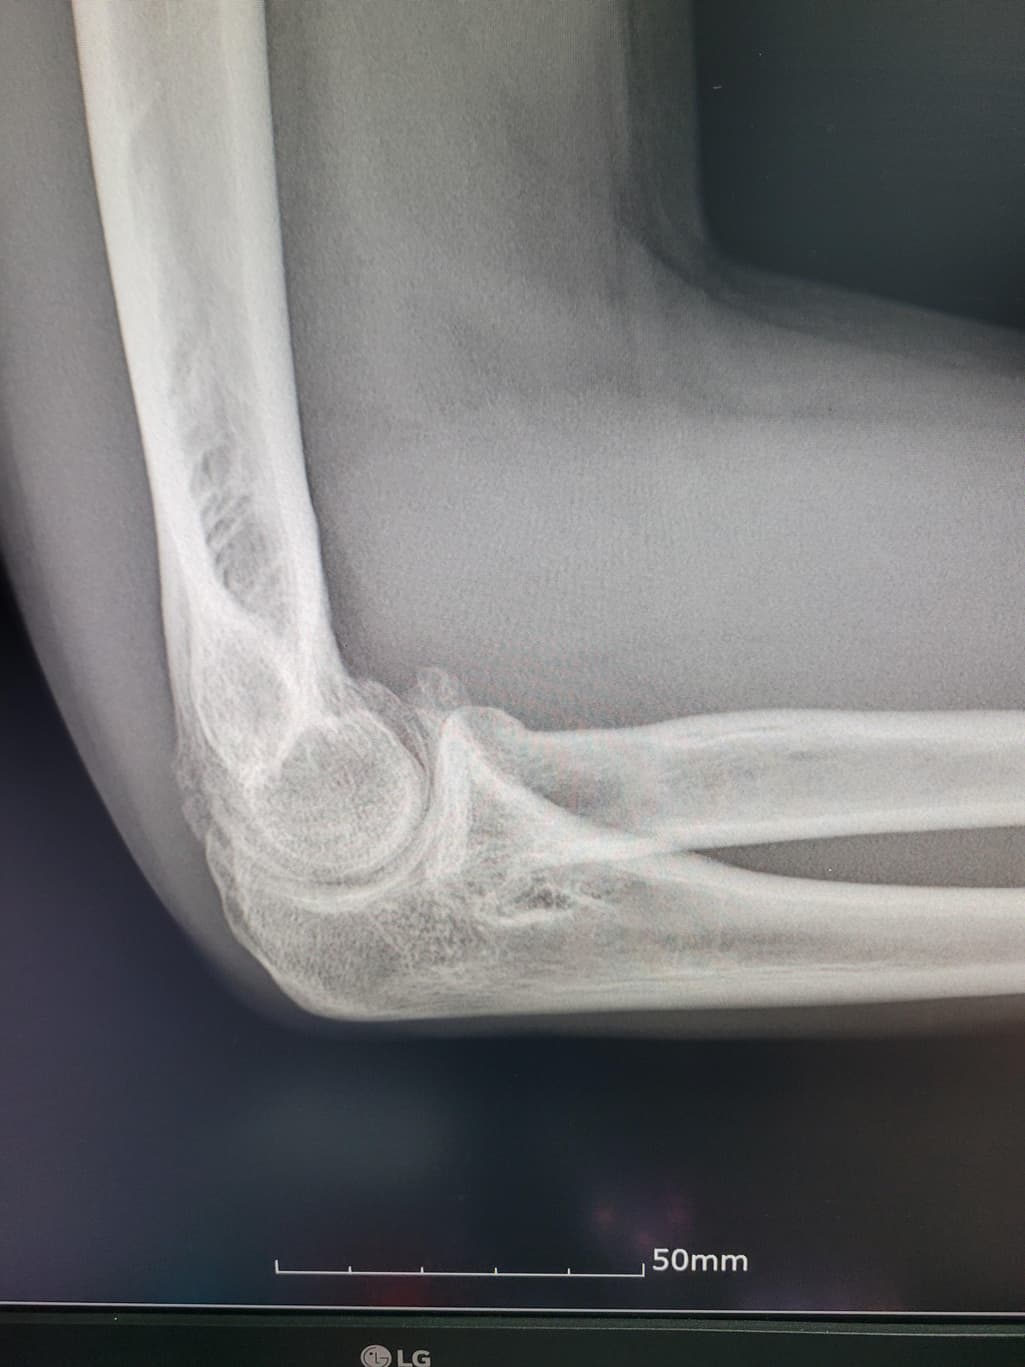

팔이 아파서 여러병원 찾아다니느라 엑스레이 사진도 복사해왔는데 1,2년 전에 비해서 팔꿈치에 동그란 게 생겼더라구여 이게 뭔지 모르겠습니다

활액막연골종은 일반적으로 엑스레이에서 뼈의 경계가 부풀어 오르거나 변형된 모습이 나타날 수 있습니다.

엑스레이에서 종양은 종종 비정상적인 경계와 불규칙한 모양을 보입니다 뼈의 구조와 혼합된 모습 일 수 있습니다.

정확한 진단을 위해 엑스레이 외에도 MRI, CT촬영과 같은 추가 검사가 필요 할 수 있습니다 전문의와 상담하는 것이 좋을 것 같습니다.

구조상 큰 변화는 없어 보입니다. 그러나, 정확한 소견은 전문의의 판독결과를 들어보시는 것이 가장정확하고, 연부조직의 염증같은 경우에는 엑스레이 보다는 초음파나 MRI와 같은 검사방법이 정확한 검사를 시행할 수 있겠습니다. 주치의와 상의 후에 판독결과나 추가적인 검사등에 대한 상담을 받아보시고, 필요시에는 검사를 받으시는 것이 좋겠습니다.